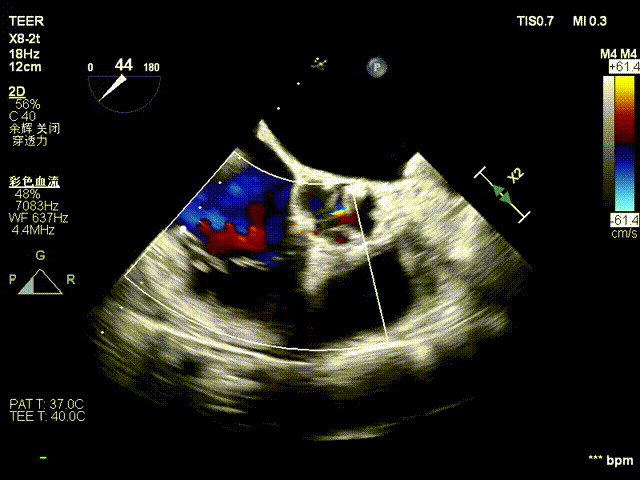

复查TTE及TEE检查进一步评估二尖瓣情况。明确为FMR( Carpentier Ⅲb型),二尖瓣后叶栓系,2区瓣叶运动(视频2),重度FMR(4+), 肺静脉逆向血流;2区后叶长度1.15cm,2区前叶长度2.46cm,AP径3.2cm,瓣口面积5.1cm²,房间隔高度3.95cm,瓣叶无钙化,二尖瓣瓣膜条件适合行TEER手术。

图1、图2:2区瓣叶长度(前叶长度2.46cm,后叶长度1.15cm)及彩色血流